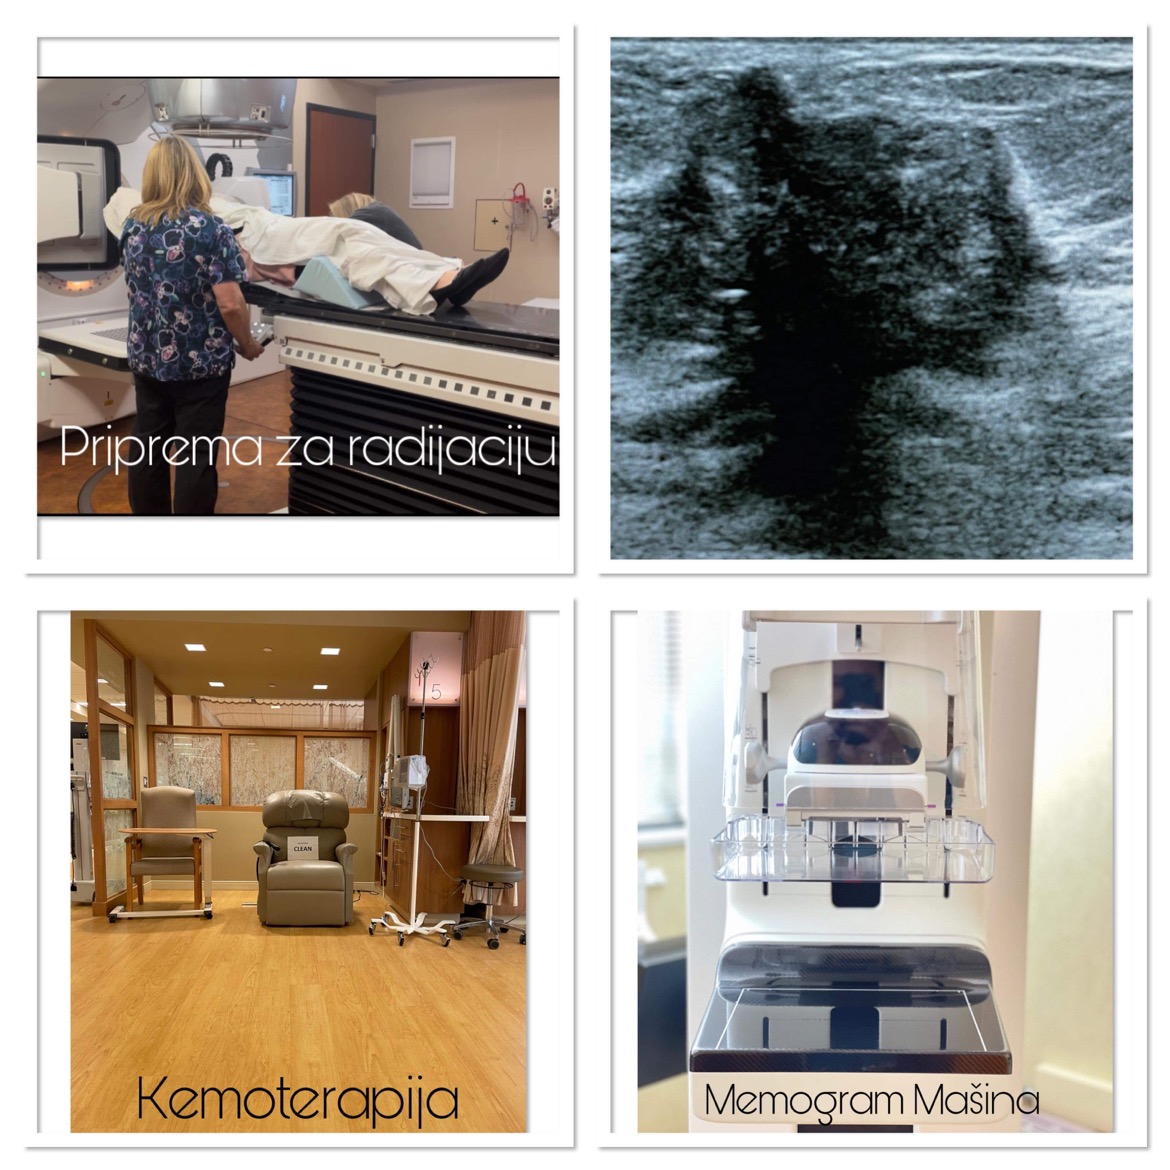

Doktorica mi je odmah rekla da mi neće moći spasiti bradavicu i naravno da će mi grudi ostati poprilično unakažene i da ih mora odstraniti gotovo 90%. Druga operacija je uklanjanje limfnog čvora gdje je rak, ispod pazuha. Nije me to uopšte potreslo, jer su to samo riječi, ali onaj dan kada sam vidjela stotine slike kod plastičnog hirurga drugih žena kojima se isto desilo, htjela sam vrištati. Samo sam šutjela i mahala glavom na sve što je govorio, a nemam pojma ni šta mi je rekao. Stotine slika mi je pokazao kako će to sve izgledati poslije operacije kad se ukloni rak. Znači prije radijacije i hemoterapije. Užas! Nisam plakala ali sam se upitala – zar se ovo stvarno dešava ili sam ja u nekoj noćnoj mori? Brzo sam se probudila dok je doktor trabunjao o proceduri o kojoj nisam zapamtila možda dvije riječi. Jedino znam da sam na kraju izašla iz kancelarije mrtva-hladna, totalno utrnula. Nisam uopće razmišljala više o hirurgu i brzo sam taj dan odlučila da ne želim rekonstrukciju grudi nego da mi se zaliječi rana pa tek onda nakon godinu ili kad već zarastu rane, tada ću pokrenuti te ostale rekonstruktivne procedure. Za sada prvenstveno želim da uklone rak s operacijom, radijacijom i hemoterapijom. Rekonstrukcija je meni lično kozmetička popravka koja je i nebitna, jer na kraju krajeva, ja se osjećam svakako sakata i to će tako biti do kraja mog života. Ovo go**o u meni vlada mojim tijelom, a ja ništa nemogu da poduzmem, ama bas ništa.